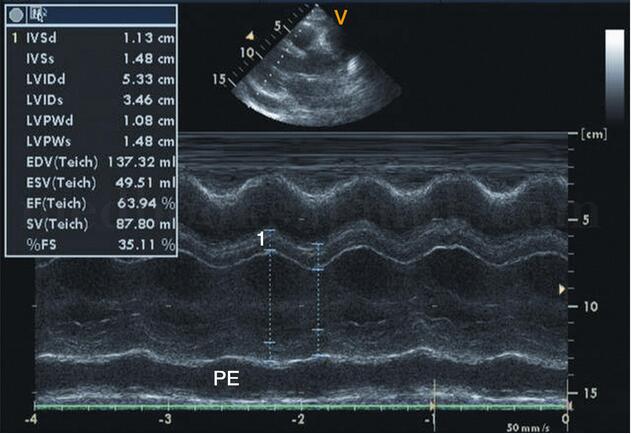

其他几种类型的超声检查也是不尽相同但各有用处,如A型超声,呈现的是一维波型,主要用于测量器官的径线,从而来判定大小,也可以鉴别病变组织的一些物理特性,如实质性、液体或是否有气体等。而M型超声采用单声束扫描心脏,观察活动界面随时间变化的一种方法。其呈现图像的y轴代表界面位置的深浅及其运动的幅度,x轴则为扫描时间的基线,这种曲线的动态变化在临床上也被称为超声心动图,可以观察心脏各层结构的位置、活动状态、结构状况等,可以辅助诊断心脏疾病,了解心肌活动能力,判断心律失常的类型等。